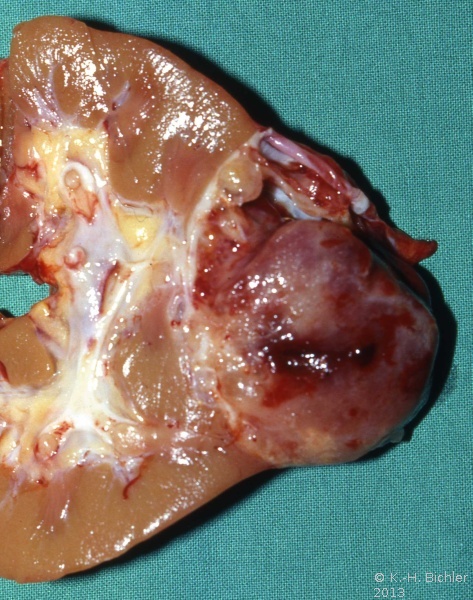

Das mesoblastische Nephrom wird im Säuglingsalter im 3.-6. Monat entdeckt, zumeist durch einen Oberbauchtumor

Literatur:Richmond, H. et al: "Neonatal Renal Tumors", J Pediatr Surg, 5, 413-417, 1970. Der Tumor ist oberflächlich glatt, z.T. bucklig, von weißgrauer Farbe (s. Abbildung 1d). Ein von der Makroskopie her vergleichbares Bild wie bei dem Wilmstumor des 8 Monate alten Mädchens. Histologisch unterscheidet sich das Nephrom vom Wilmstumor, der zumeist ältere Kinder betrifft. Es finden sich dicht verflochtene Bündel von Spindelzellen mit elongierten Kernen, die das renale und perineale Gewebe infiltrieren, Einschlüsse von Glomeruli und Tubuli in das Tumorgewebe sind häufig. In wie weit das mesoblastische Nephrom zur Gruppe der Wilmstumoren gehört, ist fraglich. Die Prognose des mesoblastischen Nephroms ist gut. Metastasen sind selten